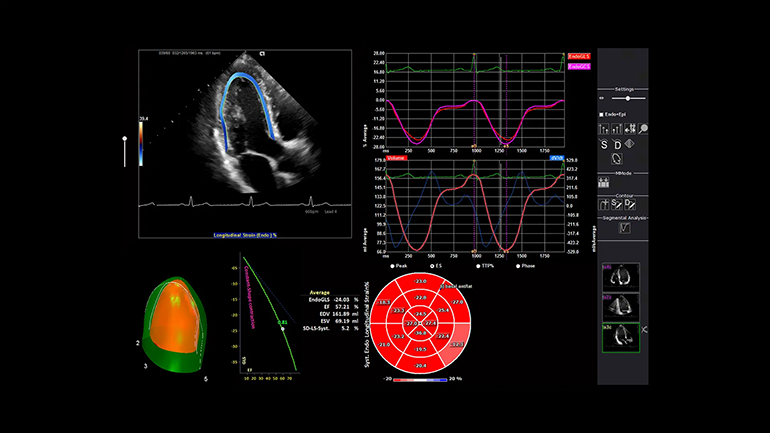

УЗИ с контрастным усилением (CEUS) с помощью визуализации с контрастным веществом. Технология импульсных последовательностей контрастного усиления эхо-сигнала от микропузырьков контрастного препарата (CPS) и технология коротких импульсов с большим механическим индексом позволяют более уверенно диагностировать очаги поражения печени. Технология визуализации векторного анализа кардиомиокинетики syngo Velocity Vector Imaging (VVI). Данная недоплеровская технология позволяет визуализировать вектор скорости и амплитуду смещения любого локуса миокарда. Таким образом, позволяет неинвазивно оценить локальную и глобальную сократимость миокарда независимо от угла сканирования.

Технология визуализации векторного анализа кардиомиокинетики syngo Velocity Vector Imaging (VVI). Данная недоплеровская технология позволяет визуализировать вектор скорости и амплитуду смещения любого локуса миокарда. Таким образом, позволяет неинвазивно оценить локальную и глобальную сократимость миокарда независимо от угла сканирования.Технологии на основе искусственного интеллекта